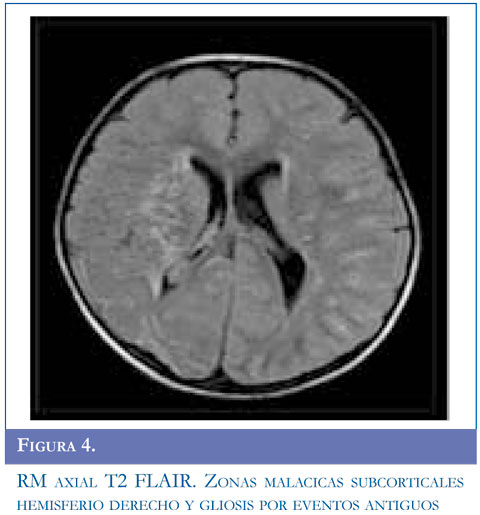

Se realizó TAC simple de cráneo que mostró evento isquémico agudo; la resonancia magnética cerebral y la angiografía por RM reportaron lesión vascular isquémica subaguda frontoparietal izquierda cortical, cambios secuelares malácicos subcorticales derechos y gliosis perilesional. Disminución de calibre de las arterias cerebrales medias más evidente del lado derecho, presencia de múltiples estructuras vasculares peri y paraventricular especialmente de lado derecho y comprometiendo región ganglio basal.

Se solicitó angiografía que mostró imágenes en humo de cigarrillo compatibles con enfermedad de Moyamoya. Compromiso bilateral de arterias carótidas internas, mayor compromiso de lado derecho. Con estos hallazgos y su condición de origen genético de base se realizó diagnóstico de síndrome de Moyamoya. Durante su evolución presentó crisis epilépticas por lo cual se inició manejo anticonvulsivante. Seguimiento expectante.